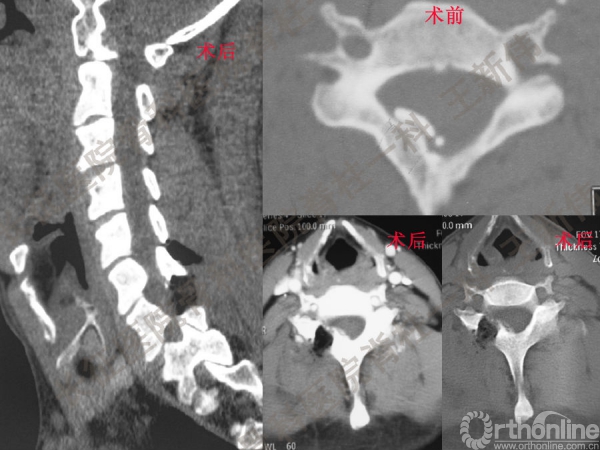

王新伟:颈椎后路通道下手术病例报告及文献回顾

颈椎后路通道下手术有哪些?颈椎后路通道下手术能做哪些事?颈椎后路通道下手术有哪些优势?长征医院骨科医院脊柱一科王新伟副教授通过临床病例报告及文献回顾,给出了他的答案——